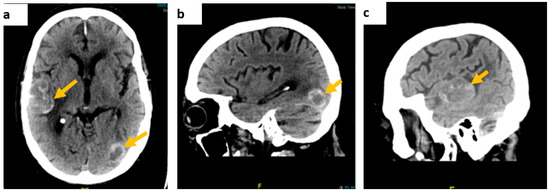

Following prompt discussion with the neuro-surgical team, dexamethasone was added to levetiracetam and the patient underwent gadolinium-enhanced MRI of the brain and contrast-enhanced CT-CAP. The latter did not show evidence of primary malignancy, whereas the gadolinium-enhanced MRI of the brain depicted several space-occupying lesions in the brain parenchyma, the largest measuring 37 × 31 × 28 mm in the right temporal area, in keeping with haemorrhagic brain secondary lesions (Figure 2).

Figure 2.

Gadolinium-enhanced brain MRI images: (a) coronal, fluid-attenuated inversion recovery (FLAIR) sequence showing a right temporal lobe lesion, (b) an axial, diffusion-weighted image (DWI), b1000 showing the temporal lesion surrounded by vasogenic oedema, and (c) an axial, T2-weighted imaging showing a high intensity lesion in keeping with the presence of either subacute stage blood products or melanin.

This patient presented with seizures and the brain MRI findings were consistent with metastatic malignancy. There was no evidence of cutaneous melanoma primarily noted on clinical examination, and the CT-CAP was not able to demonstrate the primary, highlighting some of the limitations of standard imaging techniques. FDG PET findings raised the suspicion of colorectal origin at the anorectal junction and the patient was referred to the colorectal multidisciplinary team meeting based on the most common aetiology for that location and pattern of spread, causing delay in addressing the melanoma primary, with the conclusive diagnosis later revealed by biopsy. This again illustrates the limitations of imaging alone in this condition, and the key role of histology and, particularly, immunohistochemistry, given that a substantial proportion of ARMMs have an amelanotic appearance even microscopically [14].